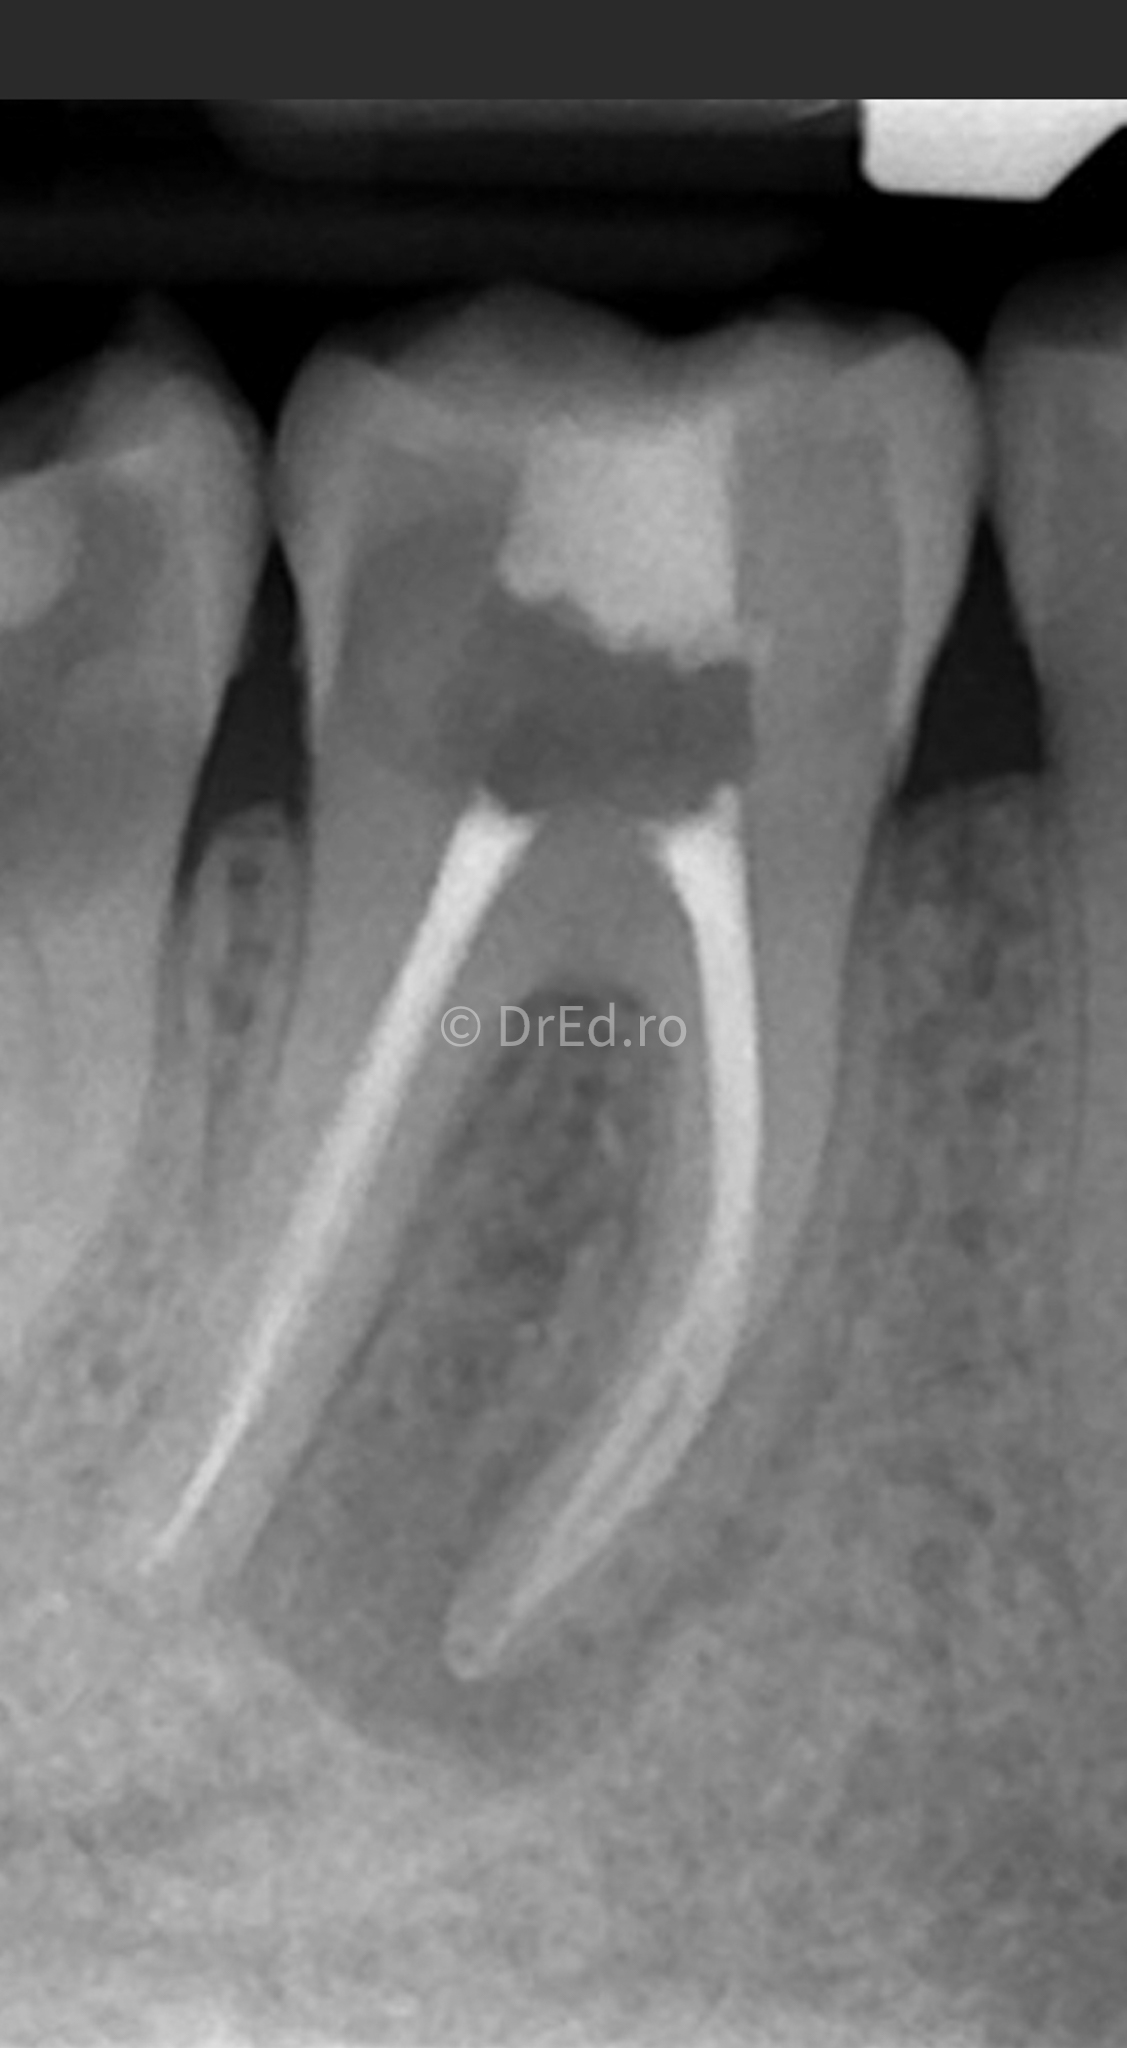

Galerie

Toate imaginile, fotografiile și radiografiile publicate pe acest site sunt protejate prin drepturi de autor și constituie proprietatea exclusivă a Dred.ro.

Aceste materiale sunt furnizate exclusiv în scop informativ și educațional și nu conțin date cu caracter personal sau informații care permit identificarea pacienților, în concordanță cu legislația privind protecția datelor cu caracter personal și GDPR.

Reproducerea, copierea, distribuirea, publicarea, transmiterea, modificarea sau orice altă utilizare, integrală ori parțială, a acestor materiale, în orice formă și prin orice mijloace, fără consimțământul prealabil scris al titularului drepturilor, este strict interzisă și poate atrage răspunderea civilă și/sau penală, în condițiile legii aplicabile privind drepturile de autor și protecția proprietății intelectuale.